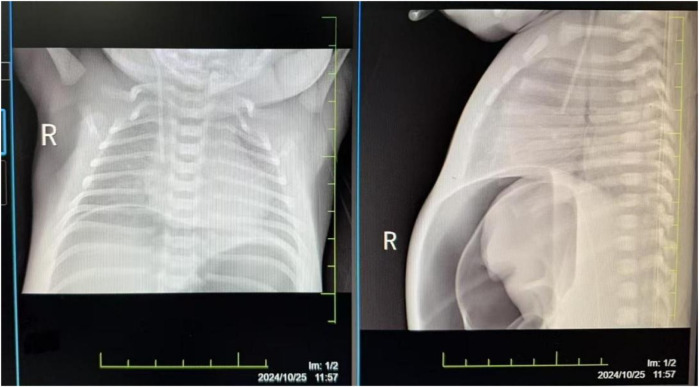

严重的新生儿窒息可导致多器官功能障碍综合征(MODS),并增加死亡和残疾风险。本病例报告描述了一个经历了15分钟严重窒息的新生儿的成功复苏和管理。男婴在妊娠36周时通过紧急剖宫产出生,Apgar评分极低(1分,5分和10分)。他接受了15分钟的复苏,包括气道清理、气管插管、正压通气、胸外按压和多次肾上腺素治疗。复苏后,他表现出严重的多器官功能障碍。婴儿接受了综合治疗,包括有创机械通气,急性肾损伤的持续肾替代治疗(CRRT),神经保护的治疗性低温,坏死性小肠结肠炎穿孔的手术治疗,以及专门的营养支持。他的病情明显改善,MODS得到缓解,出院时体重增加,进食耐受性良好。出院时的神经学评估未见明显异常;然而,长期随访正在进行中,以监测潜在的神经发育结果。本病例强调了及时复苏和细致的系统管理对于实现严重窒息和MODS新生儿良好预后的重要性。多学科团队的成功合作对新生儿的康复起了关键作用。

Severe neonatal asphyxia can lead to multiple organ dysfunction syndrome (MODS) and increase mortality and disability risks. This case report describes the successful resuscitation and management of a neonate who experienced 15 min of severe asphyxia. The male infant, born at 36 weeks' gestation via emergency cesarean section, had extremely low Apgar scores (1 at 1, 5, and 10 min). He underwent 15 min of resuscitation, including airway clearance, endotracheal intubation, positive pressure ventilation, chest compressions, and multiple administrations of epinephrine. Post-resuscitation, he exhibited severe dysfunction in multiple organ systems. The infant received comprehensive treatment, including invasive mechanical ventilation, continuous renal replacement therapy (CRRT) for acute kidney injury, therapeutic hypothermia for neuroprotection, surgical treatment for necrotizing enterocolitis with perforation, and specialized nutritional support. His condition significantly improved, with resolution of MODS, and he was discharged with weight gain and good feeding tolerance. Neurological assessments at discharge showed no significant abnormalities; however, long-term follow-up is ongoing to monitor for potential neurodevelopmental outcomes. This case highlights the importance of timely resuscitation and meticulous systemic management in achieving a favorable prognosis for neonates with severe asphyxia and MODS. The successful collaboration of a multidisciplinary team played a key role in the neonate's recovery.